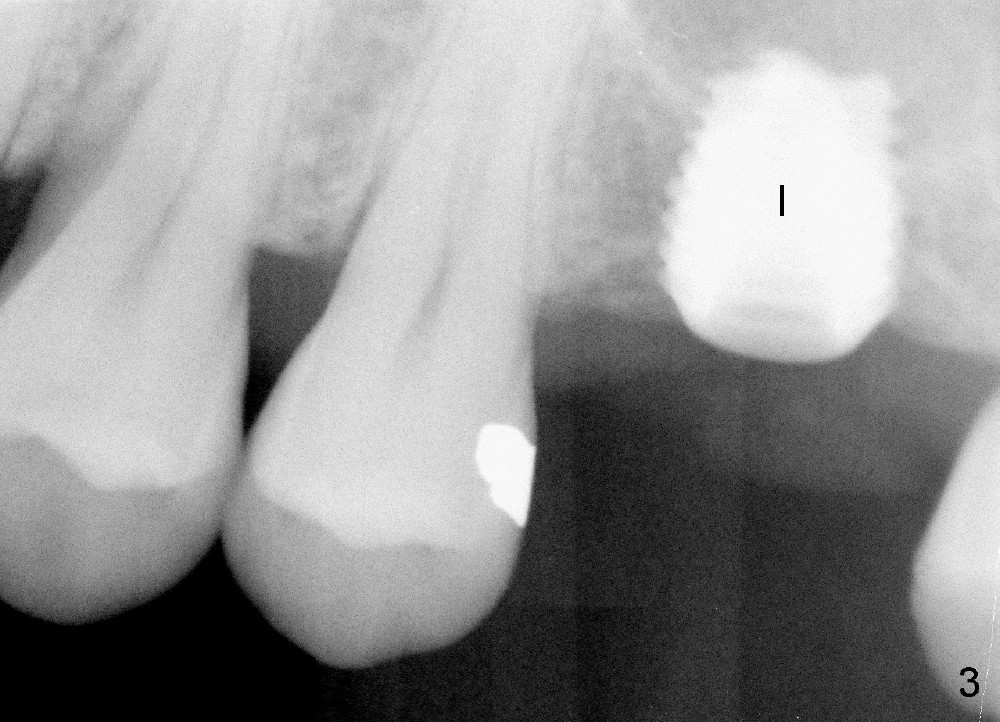

A 45-year-old man has lost the tooth #14 for a while (Fig.1); bone height is 5.4 mm. An extra wide and short implant is planned. Torus palatinus is large, suggesting that bone density should be high. A 6 mm tissue punch is chosen, but it is placed more palatal. If it were placed in the middle of the ridge, there would be no buccal keratinized gingiva (incision may avoid this issue). Additionally, the buccal portion of punch is made incomplete so that there is pedicle on the buccal side when the flap is raised (Fig.4,8: F). It is expected that the excess portion of keratinized tissue will form thick gingiva buccally. Osteotomy proves that bone is dense (Fig.2 (4.5x11 mm tap). Typical sinus lift is finished with placement of 6.4x6 mm (extra wide) bone-level implant (Fig.3, >55 Ncm). Following further torque, Fig.4 shows that the implant (I) is sub-gingival (<). Bitewings are taken to confirm that the implant plateau is at the crestal level (Fig.5,6 ^). PA shows sinus lift (Fig.7 *). The lingual aspect of the implant and healing abutment (H) is further bone grafted and covered by collagen dressing (Fig.8 *). The wound is protected with perio dressing. When the latter dislodges 7 days postop, the collagen dressing and bone graft are lost as well (Fig.10), while the buccal flap remains vital (Fig.9). The lingual exposed plateau should be able to heal normal. The collagen dressing should have been fixed in place by suture or as simple as a dental floss. There is mild nasal hemorrhage 1-2 days postop, possibly related to sinus membrane perforation and inability of Collagen Dressing to cover the perforation and contain the bone graft. When the patient returns for #9 implant placement in 3 weeks postop, the buccal flap reduces in size (Fig.11 *), while the palatal wound has healed with minimal exposure of the implant (Fig.12). Sinus graft remains in place 3 months postop (Fig.13); the buccal flap appears to have incorporated into a part of the gingiva (Fig.14). The bone density of the sinus lift appears to increase 10 days later when an abutment is placed (Fig.15 *). Although oral hygiene is pristine, there is apparent crestal bone resorption 12 months (Fig.16) and 20 months (Fig.17) post cementation, probably due to unfavorable crown/implant ratio and bruxism as well as pre-implantation bone loss (Fig.18,19). In contrast, an immediate implant in the same patient avoids pre- or post-implantation bone loss. In fact both the soft (Fig.20) and hard (Fig.21) tissues remain healthy 2 years 8 months post cementation. The sinus lift remains 3 years 8 months post cementation (Fig.22), while the crestal bone loss persists. The patients keeps complains of food impaction distal associated with bad smell 4 years 1 month post cementation. In fact the distal proximal contact is within normal limit. The bad smell is probably due to crestal bone loss (Fig.23 (pan), 24 (CT) *) and periimplantitis. Bone graft, PRF and Cytoplast membrane will be needed and fixed in place with long healing screw. When the patient returns for crown redo, he also reveals floss related gingival hemorrhage. There is pain associated with palatal sulcus probing with light gingiva erythema. Review of CT coronal section shows possible palatal (Fig.25 P) bone loss (*).